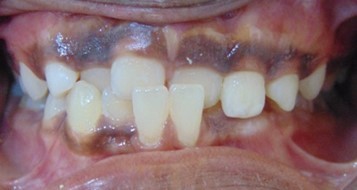

Abhinav Jain, 24Y, Duration - 8Months

Before

After

Image 1